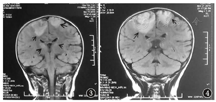

患儿,女,1岁,因"发热3 d,抽搐2次"入院。患儿3 d前出现发热,体温最高39.4 ℃,抽搐2次,抽搐时双眼上翻,四肢强直抖动,意识不清,口唇发绀,口吐白沫,第1次约1 h,第2次约15 min,抽后如常,伴轻咳,无喘息,无呕吐、腹泻,无皮疹,无鼻衄等。既往体健。2个月会抬头,4个月会翻身,7个月能坐,并萌牙,现能叫爸爸妈妈,可扶走。无药物及食物过敏史。按时接种疫苗。查体:体温37 ℃,神志清楚,反应可,球结膜无水肿,咽充血,呼吸24次/min,双肺呼吸音粗,未闻及干湿性啰音,心率110次/min,心音有力,律齐,未闻及杂音,腹软,肠鸣音正常,四肢肌力、肌张力正常,布氏征、克氏征、双侧巴氏征阴性。入院后患儿仍发热,体温波动于36.2~38.4 ℃,第3天患儿出现呕吐,呈喷射性,嗜睡,左上肢肌力下降,未抽搐。入院查血白细胞计数7.30×109/L,血红蛋白110 g/L,血小板计数254×109/L,C反应蛋白1.68 mg/L,异型淋巴细胞0.04。肝功能、心肌酶谱、血糖、血氨、血乳酸均正常。淋巴细胞亚群及免疫球蛋白检测正常。入院第8天脑脊液生化、常规、降钙素原正常。脑脊液涂片、墨汁染色阴性。脑脊液EB病毒、结核分枝杆菌、肺炎支原体、单纯疱疹病毒Ⅰ型均阴性。血培养及脑脊液培养阴性。脑脊液免疫性脑炎相关抗体(NMDA-R-A、CASPR2-Ab、AMPA1-R-Ab、AMPA2-R-Ab、LGI1-Ab、GABAB-R-Ab均阴性)、寡克隆区带检测阴性[脑脊液免疫球蛋白G 23.1 mg/L(正常范围10~40 mg/L)、血清免疫球蛋白G 5.54 g/L(正常范围7~17 g/L)、脑脊液IgG寡克隆区带阴性、血清IgG寡克隆区带阴性、脑脊液特异性IgG寡克隆区带阴性]。脑电图检查正常。入院前1 d头颅CT:平扫未见明显异常(图1)。入院第3天头颅CT示脑灰白质分界欠清,双侧额顶叶多发高密度影,伴周围水肿,双侧额顶叶缺血改变,左侧额顶叶脑沟增宽(图2)。入院第4天头颅磁共振成像(MRI)示双侧背侧丘脑形态信号异常,脱髓鞘改变,双侧大脑半球白质多发出血灶,并少许强化及周围水肿,考虑急性坏死性出血性白质脑炎可能,垂体强化欠均匀,Rathke囊残留?颅脑MRA扫描未见明显异常(图3)。入院第10天复查头颅MRI+脊髓MRI:颅内多发异常信号影,考虑出血性改变(亚急性中期),病变水肿范围较前增大,出血病变增多(图4),脊髓MRI未见异常。脑静脉核磁血管成像:窦汇形态异常,考虑先天变异。入院后诊断颅内多发病变性质待查:AHLE?惊厥持续状态,支气管炎。给予利巴韦林、头孢噻肟抗感染,止血,降颅压,地塞米松等治疗,患儿体温正常,无呕吐,无抽搐,无嗜睡,左上肢肌力逐渐恢复,临床症状缓解,生长发育同同龄健康儿童,但复查头颅MRI好转不明显,家长要求出院,院外随访2个月病情未进展,患儿无抽搐,可独走。

脑脊液检查示颅内压升高,细胞数增加或正常,糖和氯化物正常。该患儿脑脊液检查未见异常。患者早期CT可正常,也可显示广泛的脑组织水肿及白质内低密度灶,可夹杂点状高密度影。MRI的T1加权像表现为广泛的脑组织水肿,单侧或双侧后额部、颞叶或顶叶白质的多发低密度灶,部分病灶可融合成片,从脑室周围延伸至皮质下白质及灰白质交界处,可有明显占位效应[2,3]。MRI的T2加权像和液体衰减反转恢复相对本病更敏感,可见双侧多灶性白质高信号,广泛高信号白质水肿内有多发的斑点状低信号,提示不同阶段的出血[5]。轻症患者脑组织活检实施困难时,可通过头颅影像学检查,做出早期诊断,做出积极治疗,对于改善患者预后有很大帮助。该患儿早期行头颅MRI及CT检查,经积极给予脱水降颅压、激素等治疗后,临床症状改善,复查头颅MRI未见明显改善,考虑可能与影像学检查滞后有关。